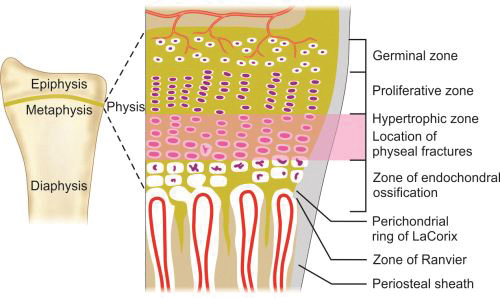

Cortical bones are long bones of the body like femur or humerus and the small bones of hand and foot like metacarpals and metatarsals. Long bones of a child (Fig. 1.12) are divided into epiphysis, physis or growth plate, metaphysis and diaphysis. Epiphysis, physis and metaphysis are present at both ends. In mature bone epiphysis fuses with metaphysis and growth plate gets replaced by bone.

Physes: Physis or growth plate is a thin region of actively growing bone cells between the epiphysis and the metaphysis in a growing bone. This is present on both the end of the long bones and responsible for the longitudinal growth of the bones. It consists of four zones (Fig. 1.13):

- Germinal zone/Resting zone

- Proliferative zone

- Hypertrophic zone

- Zone of endochondral ossification.

Germinal zone provides the developing chondrocytes which divide and get organized into columns in proliferative zone. Both germinal and proliferative zones are rich in extracellular matrix. In hypertrophic zone chondrocytes stop mitoses and undergo hypertrophy. This is the weakest zone of physis and most physeal injuries occur through this plane.

Physis is connected to epiphysis and metaphysis by the zone of Ranvier and perichondral ring of LaCorix. Zone of Ranvier contains germinal cells, which is responsible for circumferential growth of physis. Ring of LaCorix is a fibrous structure that is connected with zone of Ranvier and periosteum of metaphysis.

-

Metaphysis: It is the junction between the growth plate and the diaphysis. It consists of both cancellous and cortical bone.

-

Diaphysis: It is the region between the two metaphyses. It consists of compact cortical bone and has a medullary canal which consists of marrow. This portion of the bone is responsible for the strength of bone for weight bearing and movement.